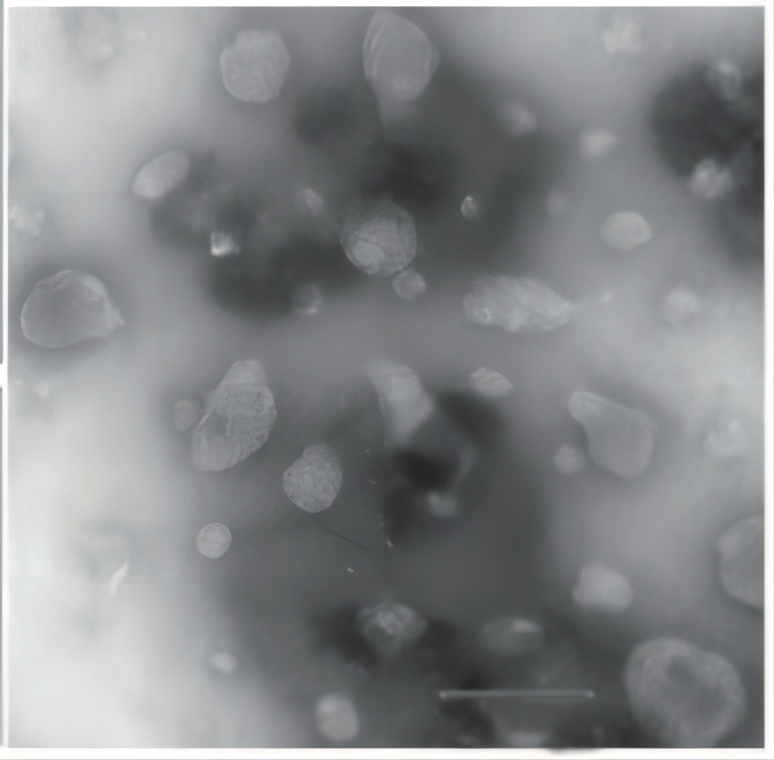

基于脂质的液晶纳米颗粒(LCNP)是另一种能够提高疏水性和亲水性药物的生物利用度的递送系统。这些是通过将非层状液晶基质进行高剪切能量分散到水相中制备的自组装结构。LCNP 的粒径是需要适当分析和控制的重要物理化学性质。Nicomp3000 系列纳米粒度仪已成功用于确定 LCNP 分散体中的平均大小和聚集体的存在。4 将紫杉醇加入 LCNP 分散体中并通过 Nicomp3000 系列纳米粒度仪和 TEM 分析,参见图 3。

图 3. LCNP 分散体的 Nicomp 和 TEM 结果,版权复制自4

TEM 图像表示较小的近 25nm 颗粒和 100nm 范围内的较大颗粒的双峰粒度分布 。较高的 Nicomp 结果是高斯强度分布平均值迫使整个分布成为一个峰值。较低的 Nicomp 结果利用专有的 Nicomp 非负最小二乘算法来报告更高的分辨率和更准确地描述实际粒度分布的双峰性质。突出了 Nicomp3000 系列纳米粒度仪的一个主要优点⸺即使在浓度低至 0.2 mg/mL 时也能解析多峰分布。5